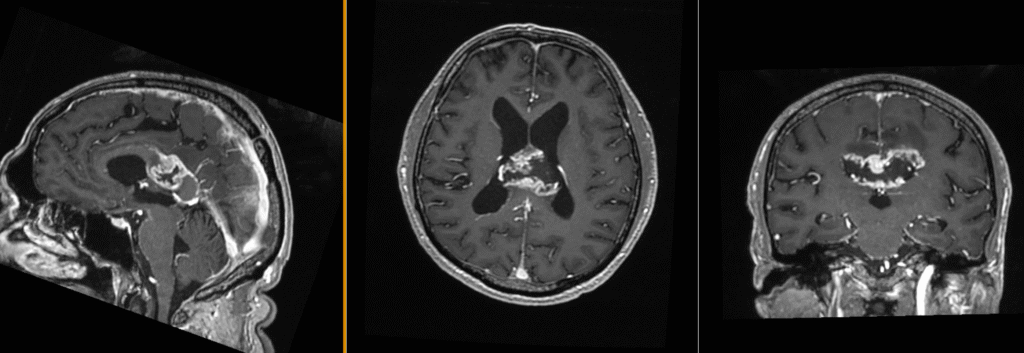

La nivel imagistic, glioblastomul apare adesea ca o leziune relativ bine delimitată, cu captare inelară de contrast și necroză centrală. Pentru ochiul neavizat, aceasta poate sugera o tumoră care ar putea fi „scoasă complet”. În realitate, ceea ce vedem pe RMN reprezintă doar componenta cea mai densă tumoral.

Imagistica – instrument esențial, dar imperfect

RMN-ul cerebral este standardul diagnostic, dar trebuie interpretat în context.

Pe lângă secvențele convenționale, tehnicile avansate aduc informații suplimentare:

- perfuzia evidențiază angiogeneza tumorală

- spectroscopia reflectă metabolismul celular

- DTI (tractografia) arată relația cu tracturile din substanța albă

Cu toate acestea, niciuna dintre aceste metode nu poate delimita complet infiltrarea microscopică. De aceea, planificarea chirurgicală și terapeutică trebuie să țină cont de această limitare.